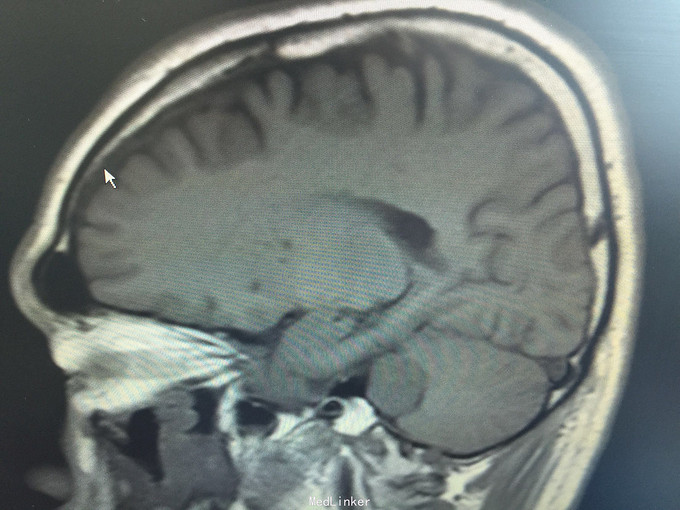

男,52岁,以“左耳鸣、听力下降1年余”入院。 现病史:1年余前看电视时出现左耳鸣、听力下降,左耳听电视声音时听不清,较右侧明显下降,未在意,之后听力下降逐渐至丧失! 既往史:既往高血压、糖尿病病史,长期吸烟病史。 家族史:无特殊!

查体:BP:150/90mmHg,心肺腹未见异常,神清语明,左耳听力丧失,无面瘫,双瞳孔等大正圆,直径约3.0mm,光敏,四肢肌力5级,肌张力正常,巴氏征R-L-。

1.左侧听神经瘤